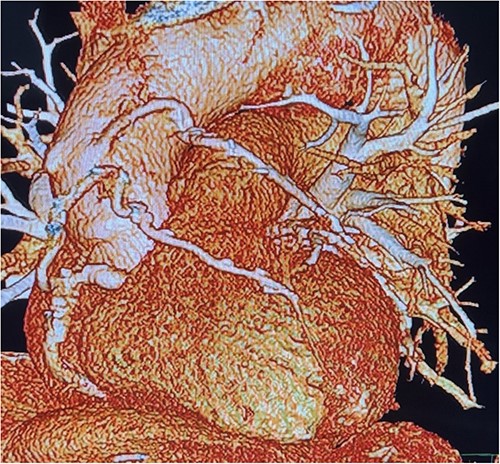

Before resternotomy, a cardiopulmonary bypass was performed via the right common femoral artery and vein. The RIMA was harvested in a semi-skeletonized fashion because skeletonized IMA is in general, longer than pedicled IMA. However, the RIMA could not reach the LAD in the present case due to cardiomegaly. Therefore, the proximal end of the RIMA was cut to use as a free graft. Subsequently, the proximal portion of the patent RA graft was tried to dissect as a proximal anastomosis site, but it was not possible due to severe adhesion of the surrounding tissue. Therefore, we decided to anastomose the proximal RIMA to the proximal right coronary artery (RCA) as the inflow site. The distal RIMA was anastomosed to the LAD as usual (Fig. 1). The postoperative course was uneventful, and the patient was discharged 11 days after the operation. A 3-month postoperative coronary angiogram showed the patency of the RA and RIMA conduits (Fig. 2). Moreover, from coronary computed tomography angiography after 6 years, it was confirmed that it was still patent (Fig. 3).

The free RIMA was anastomosed to the mid-part of RCA and bypassed to the distal LAD.